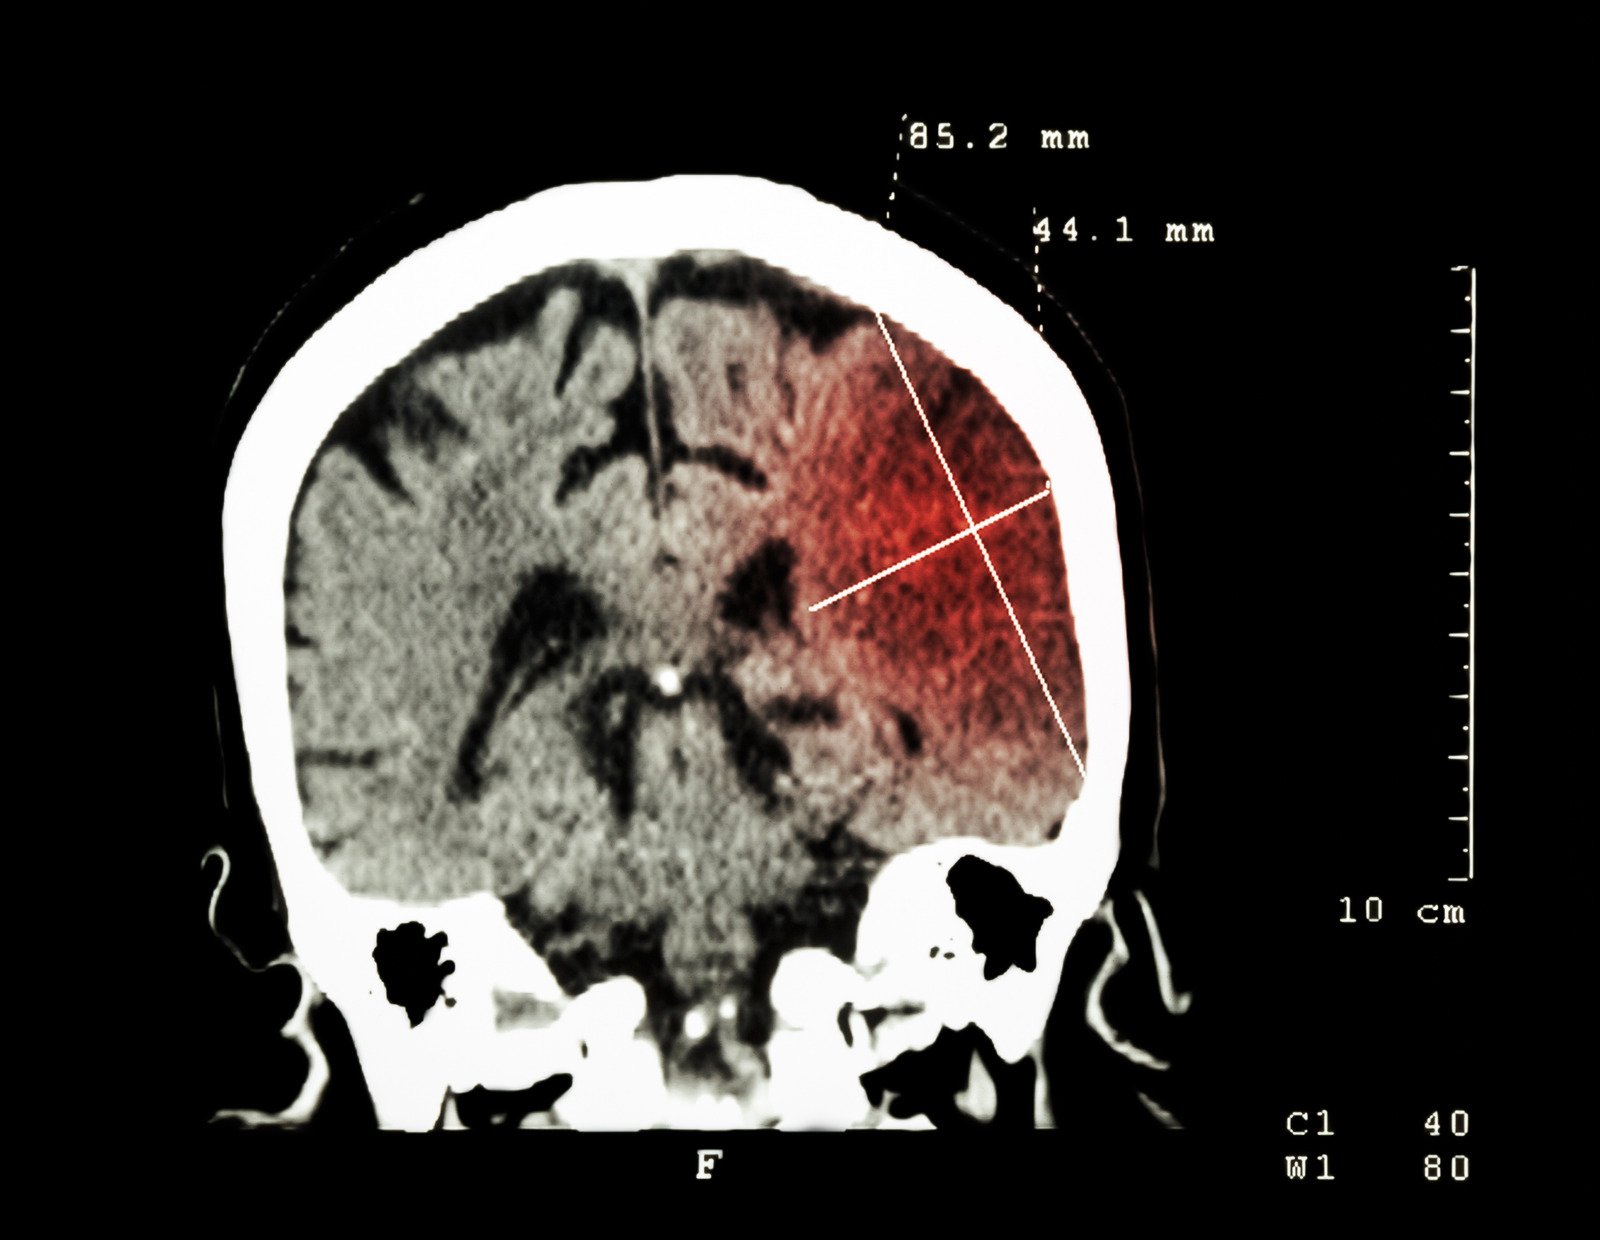

진단 방법

뇌경색은 주로 영상 촬영을 통해 진단됩니다.

가장 일반적인 방법은 CT(컴퓨터 단층 촬영) 스캔과 MRI(자기 공명 영상)입니다.

이러한 검사들은 뇌의 혈류 차단 상태를 확인하고 손상된 부위를 정확하게 파악하는 데 도움이 됩니다.